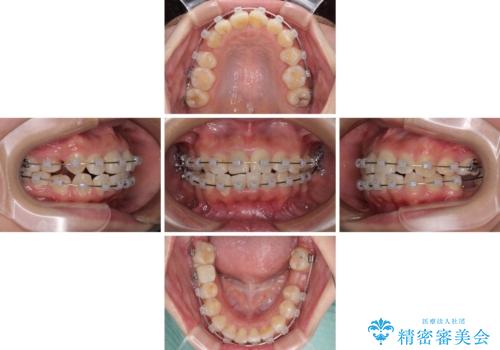

口元の突出感は少なく、下顎の叢生は軽微なものであったので、叢生の強い上顎左右の小臼歯を1本ずつ抜歯し、ワイヤー装置にて矯正治療を行うこととしました。

矯正治療を行う前に、根管治療の必要な上顎前歯と下顎大臼歯の根管治療を行い、矯正治療の途中で下顎の欠損部にインプラント埋入することとし、矯正治療後に補綴治療を行うこととしました。

矯正治療中にインプラント埋入を行うなど、余計な時間や無駄のない治療を行うことができました。